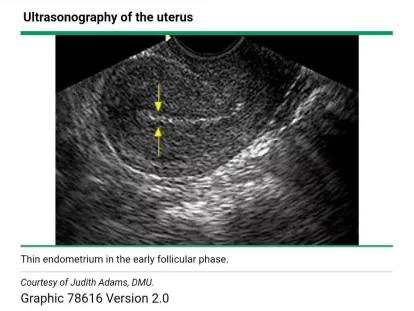

卵泡期月经过后,由于功能层脱落,这个时候子宫内膜厚度就会变得很薄,一般4-5mm。

超声下表现为薄的强回声线。